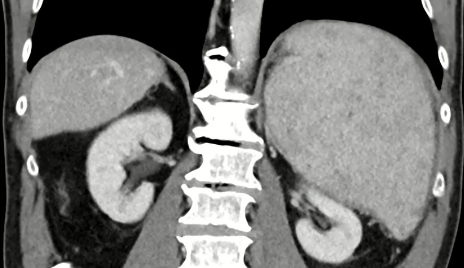

栓塞材料的可及性(例如病灶栓塞材料的可到达性)accessability (e.g. reachability of the nidus) 栓塞的预期深度intended deepness of embolization 如果需要让栓塞填满最后1mm 预期效果(例如:门静脉栓塞的炎症)intended effect (e.g. inflammation in PVE) 凝血状态(达到止血效果所需的时间)coagulation state (duration until hemostasis) 并发症(过敏、心律不齐、肺动脉高压、肝纤维化等)comorbidities (allergies, arrythmia, pulmonary hypertension, lung fibrosis etc.) 处于危险中的结构(包括下游部分-downstream和反流部分) structures at risk (downstream & backwash) 靶病变定位(浅层与深层) target lesion localization (superficial vs. deep) 不会选择一些会引起炎症的东西,因为那会病人来说真的很痛苦浅层病变 栓塞所需的速度(例如:危及生命的出血情况)required speed of embolization (e.g. life threatening hemorraghe) 院外专业人员(DSA技术人员和介入放射科医生)local expertise (technicians & IR's) 可用性与定价 availabilty & pricing Patient assessment for the choice of the ideal liquid emboli 影像学 62岁 男性

腹腔侧支循环